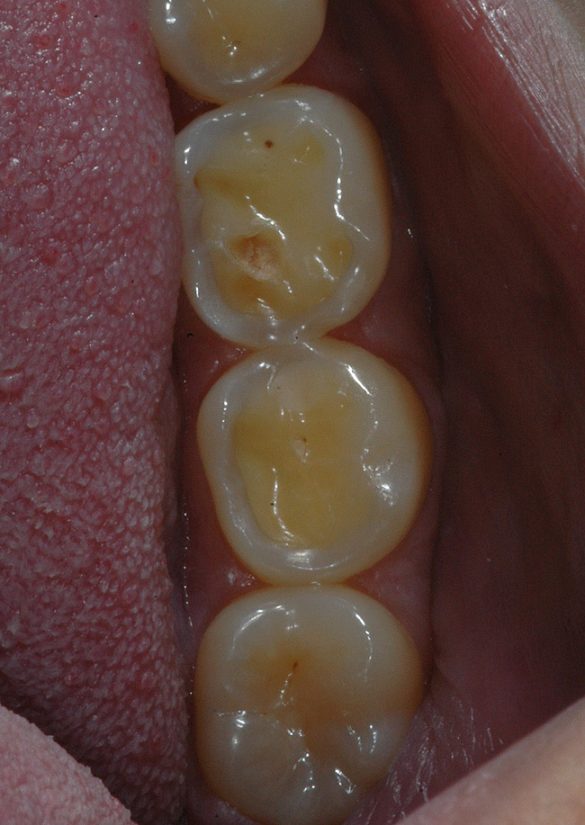

În cursul examinării clinice s-a notat o igienă orală satisfăcătoare. Pacientul prezenta coroziunea suprafeţelor ocluzale şi orale la dinţi maxilari şi mandibulari posteriori (fig. 1). Avea, de asemenea, arii expuse de ţesut dentinar (fig. 3) şi restaurări din amalgam compromise în lipsa sprijinului adecvat.

În prezentarea de faţă, deşi pacientul a utilizat o gutieră nocturnă pentru evitarea uzurii cauzate de bruxism, dinţii cu restaurări din amalgam prezentau o suprafaţă curată şi lipsită de pete colorate, sugerând un proces activ de eroziune.1 Se pot lua în considerare tratamentele conservatoare pentru sensibilitatea dentinară; adesea devine necesară înlocuirea structurii dentare pierdute. În cazul de faţă, factorul care a stabilit necesitatea tratamentului a fost reprezentat de pierderea structurii dentare, asociată cu hipersensibilitate.